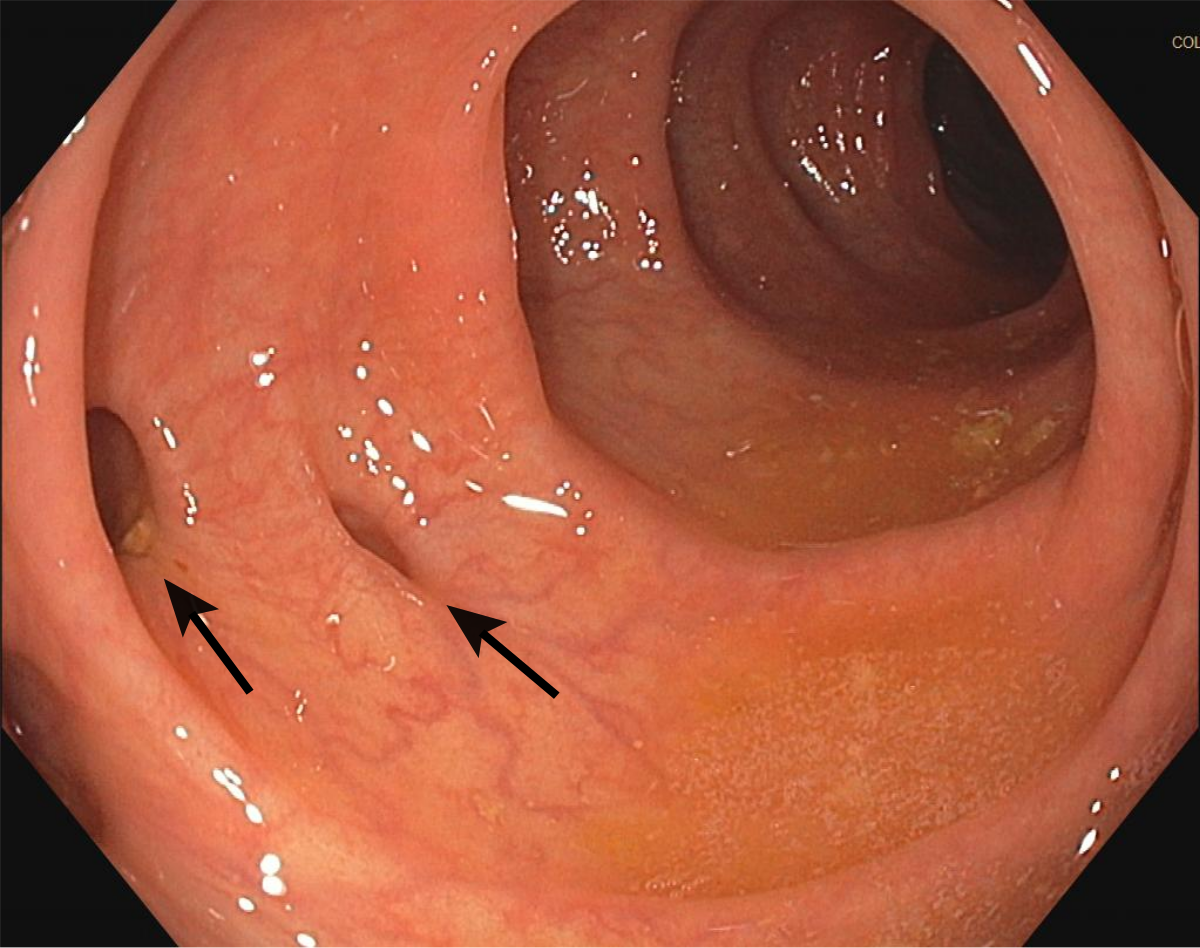

高雄市立聯合醫院外科陳培桓主治醫師解釋,大腸憩室症發生的原因以「後天性」居多,主要是因為大腸內壓力的異常升高,加上腸壁肌肉的結構弱化,導致像吹氣球一樣,在大腸外側形成像囊狀的構造,而大腸內側的腸黏膜,則被推擠穿過腸壁肌肉層形成凹窩。每個人的大腸或多或少都會有大腸憩室的存在,大部分的人都不會有甚麼感覺,或者只有非常輕微的症狀,例如偶而出現腹脹、腹痛、便秘或腹瀉、過度排氣和食慾不振。

大腸憩室症好發於中老年人,而且發生率會隨年齡增長而上升;平時不愛攝取纖維質食物或長期便秘的人,也很容易發生這種病症。值得一提的是,這個疾病呈現「東西有別」的現象,西方國家的人一般都是發生在左側(乙狀)大腸,而東方國家的民眾則較常發生在右側(盲腸)大腸。右側大腸的憩室症因為發炎的症狀和疼痛位置與盲腸炎相似,所以才容易被誤判為盲腸炎。

大腸憩室症主要是因為大腸內壓力的異常升高,加上腸壁肌肉的結構弱化,導致像吹氣球一樣,在大腸外側形成像囊狀的構造,而大腸內側的腸黏膜,則被推擠穿過腸壁肌肉層形成凹窩。